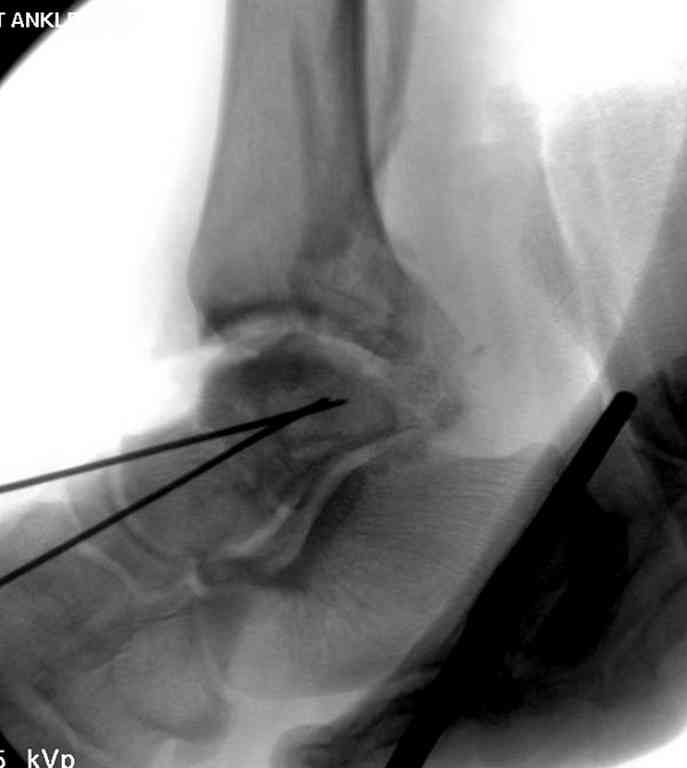

Здесь на фото примеры:

Переломовывих тарана с повреждением медиальной стороны. Через 4 часа после поступления проведена репозиция и фиксация тарана после Irrigation&Debridment. Частичное несращение медиальной лодыжки не беспокоит, вернулся к активному образу жизни. Полная нагрузка разрешена через 11 недель. Финальные снимки через 11 месяцев.